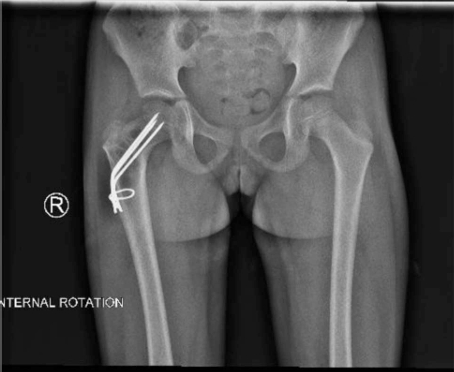

一名 5 岁女童因右下肢外伤后 3 周出现右髋疼痛并伴有跛行而就诊于我院急诊科。体格检查发现,其右髋存在疼痛,且在髋关节旋转时疼痛加重。影像学检查显示,右侧股骨颈可见一大型溶骨性病变,向转子区延伸,并伴有股骨颈应力性骨折及内翻移位(图 1 和图 2)。

手术技术:经股骨近端外侧入路,逐层分离直至显露骨质。在转子区前侧皮质上使用钻头开窗,保留外侧皮质以用于固定,随后对病灶进行刮除,远端显露股骨髓腔,并取样送病理活检。其后,自外侧皮质向股骨头方向钻入 3 枚直径为 2 mm 的克氏针,至软骨下骨约 5 mm 。随后将克氏针弯曲成较大的弧形,以防止回弹及内翻移位,并加用一根环扎钢丝穿过股骨,以帮助增强稳定性(图 3)。最后,在病灶区域填充异体骨移植材料。切口关闭后,考虑到患儿年龄,予以半髋人字石膏固定 6 周(图 4)。若患者年龄更大且配合度更好,则可不使用石膏固定(见第二个病例)。术后 3 个月,拆除人字石膏并复查影像学检查(图 5)。